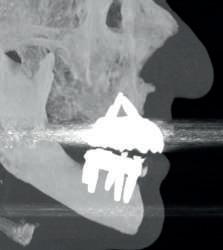

According to the prosthetic planning in the co diagnostix software, it is decided to extract the remaining upper teeth, leaving two teeth temporarily for stabilisation of the surgical guide and as a reference for the immediate scanning after the placement of 4 single-stage implants (Fixo. Oxy. Italy).

In the lower part the extraction of the remaining teeth is planned and the immediate placement of 6 implants (dynamic hex. Cortex . Israel) and and the immediate placement of Multi Units Abutments (MUA. DAS. Dynamic Abutment Solutions. Spain). However, when planning for the lower implants at the same level, there is a collision of the sleeves with the bone that prevents the placement of the implants at the same level (fig. 6), so the offset of the anterior implants is modified to ensure the correct position in the guide, avoiding interference with the bone and placing the implants at the same level (fig. 7).

In the maxillary case, the implants with integrated MUA Abutment (monoimplantes fixo . oxy italia) are placed and scanning is performed before extractions of the remaining teeth that will serve as a reference for the scan and the position reference in the design software.

Once the surgical guide is stabilised, the osteotomies and placement of the lower posterior implants are performed, while the length of the anterior implants is changed in the drilling sequence according to the modified offset, which corresponds to the mounter, colour-coded according to the length of the offset.

Immediately after implant placement, the MUA Abutments are placed (Dynamic Abutment Solutions)

The immediate prostheses are milled in PMMA and fitted on their corresponding bases, adjusted and radiographically checked for proper seating.

After 6 months the patient returns and records are taken for the final prosthesis. In this case the lower prosthesis is made of a titanium bar and a PMMA superstructure and the upper part is made of a titanium substructure and a zirconia structure.